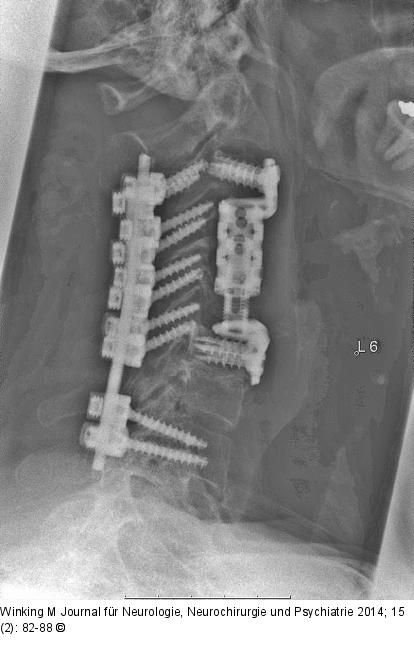

Abbildung 9: Rheumatische Wirbelsäule Seitliche Röntgenaufnahmen nach ventraler Spondylektomie und kombinierter ventrodorsaler Stabilisierung durch distrahierbaren Titankorb mit dorsalem Schrauben-Stab-System. |

Seitliche Röntgenaufnahmen nach ventraler Spondylektomie und kombinierter ventrodorsaler Stabilisierung durch distrahierbaren Titankorb mit dorsalem Schrauben-Stab-System. |